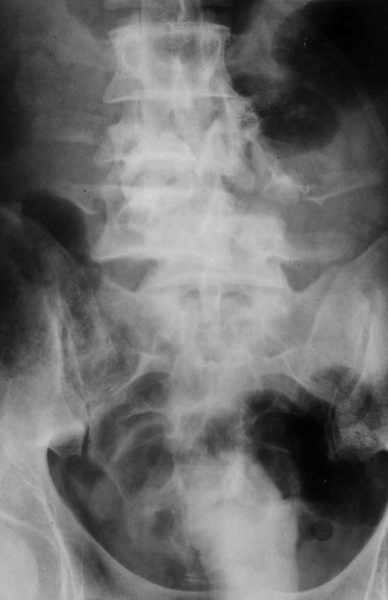

Поступил мужчина 37 лет. Автотравма - перевернулся на машине.

При поступлении состояние тяжёлое. Диагноз: "Оскольчатый перелом тела L3 позвонка, переломы корней дуг L3, l4 позвонков, дислокация (птоз) тел l3, L4 позвонков, множественные флотирующие переломы рёбер слева, гемопневматоракс". При всём при этом практически никакой неврологической симптоматики (легкое онемение по наружной поверхности левого бедра) функции тазовых органов не нарушены, движения в нижних конечностях сохранены. КТ сделать нет технической возможности, сканы рентгенограмм плохого качества поэтому высылаю скиаграммы. Рентгенограммы пришлю позже. Встало два вопроса: Теоретический - как грамотно сформулировать диагноз позвоночной травмы? Практический - тактика оперативного лечения позвоночной травмы. В настоящий момент сосстояние пациента стабилизировалось. С уважением Андрей Стасюк

1

Высылаю рентгенограммы. Спасибо за рекомендации. Наша тактика согласуется с вашими рекомендациями за исключением транспедикулярной фиксации - у данного пациента на наш взгляд предпочтительнее наружная транспедикулярная фиксация (Курганский аппарат). Погружная конструкция предпологает одномоментную репозицию до выполнения забрюшинного доступа и ревизии переломов что теоретически может привести к повреждению дурального мешка и корешков. АВФ позволит восстановить ось позвоночника и смещение по длине непосредственно под контролем глаза на этапе внебрюшинного доступа. Сколько сегментов замыкать? Я думаю может потребоваться замкнуть и сегмент L2-L3. Предполагается использовать тело L4 для костной пластики таким образом, чтобы ширина спиномозгового канала на уровне оперированных сегментов была увеличена. Фиксация тел позвонков вентральной пластиной.